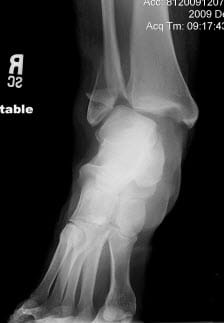

- Inside, we get referred up to Orthopedics. Supposedly they are going to take x-rays at 2:30, prefatory to a 3:00 meet with the Orthopod. Instead, we hang out until close to 4 before we see the Orthopod, he sends us across the hall for x-rays, we go back, and he informs us that (a) yes, both bones are broken, (b) Littleton Adventist did a piss-poor job in setting the bones because there’s still a big piece of bone pressing outward. Ick.